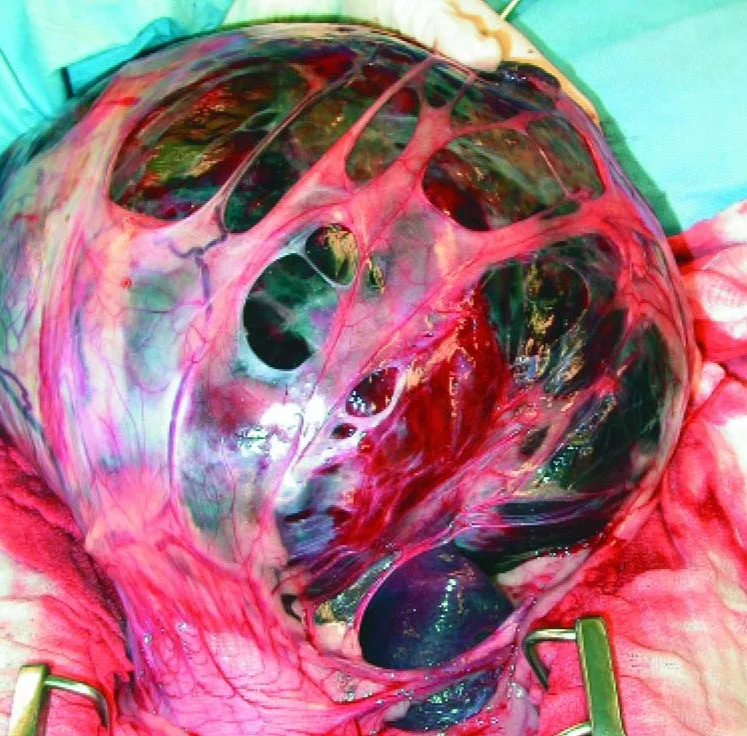

Neoplasia

Omentum adhering to splenic masses can harbor a substantial number of vessels that require ligation (Figure 2). Ligate and remove these adhesions well away from the mass first before attempting pedicle ligation. It is acceptable to ligate any main splenic branches attached to, or encompassed within, the tumor to help ensure removal of all gross evidence of neoplasia, as long as adequate collateral gastric blood supply is available.